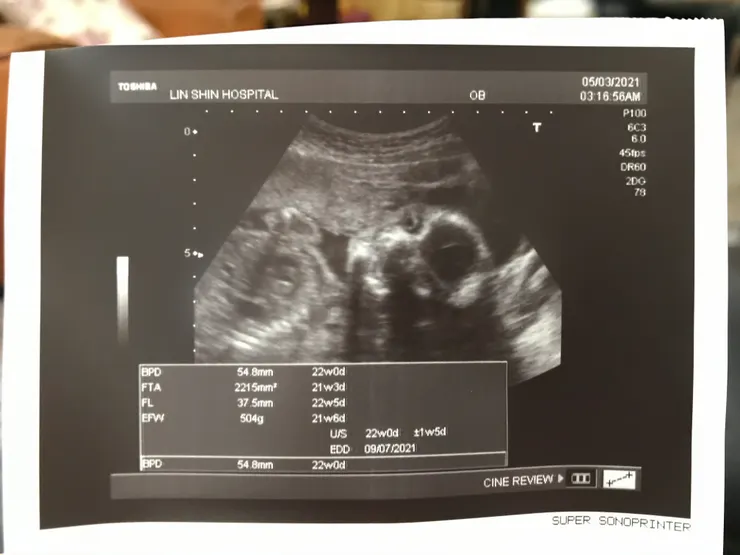

經期延遲10天一驗就有了

所以算是很早發現

20週開始感覺到胎動

性別──不知道

醫生沒講、我們沒問